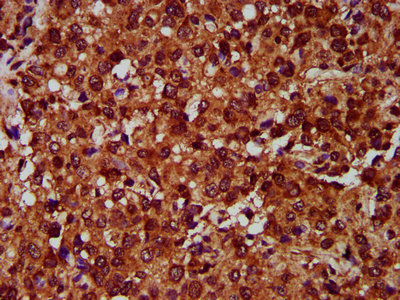

IHC image of CSB-PA007649LA01HU diluted at 1:400 and staining in paraffin-embedded human glioma performed on a Leica BondTM system. After dewaxing and hydration, antigen retrieval was mediated by high pressure in a citrate buffer (pH 6.0). Section was blocked with 10% normal goat serum 30min at RT. Then primary antibody (1% BSA) was incubated at 4°C overnight. The primary is detected by a biotinylated secondary antibody and visualized using an HRP conjugated SP system.